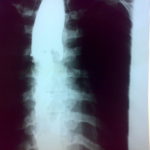

食道がん

食道がんとは、食道の組織内に発生するがんの総称です。